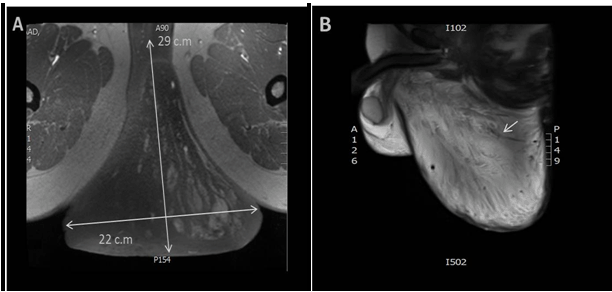

A 45-year-old male presented with a swelling in the perianal area that had begun to grow four months previously. He complained of pain, and problems defecating. Physical examination located a soft lump in the perianal area, with ill-define edges near to the posterior midline (Figure 1). Although it is a rare condition, one of our preliminary differential diagnoses was lipomas. Other differential diagnosis was possible Desmoids Type Tumor. Magnetic resonance imaging (MRI) scan of the pelvis showed a large flask shaped mass sagging from the perineum, with fat lobules apparently originating from perineum, extending into the intergluteal cleft. There was concern about the swirled appearance noted post contrast study, which suggested possible diagnosis of a myxoid type tumor and less likely a lipoma (Figure 2A-B). Surgical excision of the mass was performed. The gross appearance of the specimen was a disoriented mushroom shaped mass, about 380 grams in weight, with a fatty cut surface (Figure 3). Microscopically, it showed an ill-defined tumor composed of small spindle cells embedded in an abundant myxoid stroma interspersed with a thick wall and hyalinized blood vessels. There was no evidence of mitotic activity or nuclear atypia (Figure 4A-C). Based on these histological features, a diagnosis of aggressive angiomyxoma (AAM) was confirmed. | ||||||

Aggressive angiomyxoma (AAM) is a rare benign soft tissue tumor of mesenchymal origin, characterized by its locally infiltrative nature and high recurrence rate. It was given this name due to the pathological findings of the stellate and spindled cells, along with variable-sized blood vessels, which were intricately entwined within a myxoid matrix [1]. This presentation occurs predominantly in woman of reproductive age (female to male ratio of approximately 6:1), and exclusively in the pelvi-perianal region. To our knowledge, only 43 cases occurring in men have been reported in literature [1]. In men, AAM usually involves the scrotum (38%), spermatic cord (33%), and perineal region (13%) [2]. Although clinical diagnosis of AAM may be difficult, the typical MRI features of AAM are swirled strands, aligned with the craniocaudal axis. This particular imaging feature is caused by a stretching of the fibrovascular stroma [3]. Confirmation of diagnosis is based on a histopathology study. AAM should be distinguished from other benign, potential lesions with low local recurrence, and malignant tumors with widespread metastatic potential. Surgery is the mainstay of treatment for AAM, although achieving negative resection margins is complicated, because of the infiltrative nature of the tumor. Local recurrence rate falls between 36% and 72% and is usually seen in the first three years. Recurrences of the disease are usually controlled with surgery [1]. Several reported attempts at using chemotherapy and radiotherapy as part of the treatment protocol for AAM have proved disappointing; probably due to the low mitotic activity/growth fraction of cells. Primary treatment with GnRH agonists has proved successful, as many of angiomyxoma are positive for estrogen and progesterone receptors [4]. However, the duration of the responses and an optimal treatment schedule are still unknown [1]. | ||||||